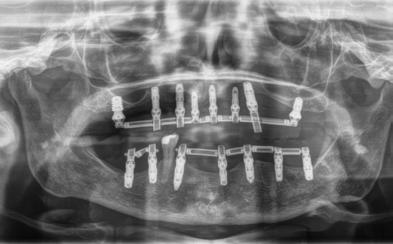

En la radiografía panorámica se ven 24 órganos dentales (Figura 12) después de realizada la cirugía osteotomía Lefort I maxilar de avance y una mentoplastía; las cuatro placas de fijación con sus respectivos microtornillos en el maxilar líneas de color rojo, la fijación con alambre quirúrgico de acero inoxidable señalados azules.

Figura 11. Radiografía lateral de cráneo. Figura 12. Radiografía panorámica.